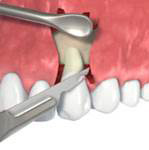

Nejlepším materiálem pro augmentace je vlastní kost pacient, kterou můžeme získat

např. odběrem z dolní čelisti pacienta. Jedná se o velmi šetrný, nenáročný výkon, který pacienta nijak nezatíží.